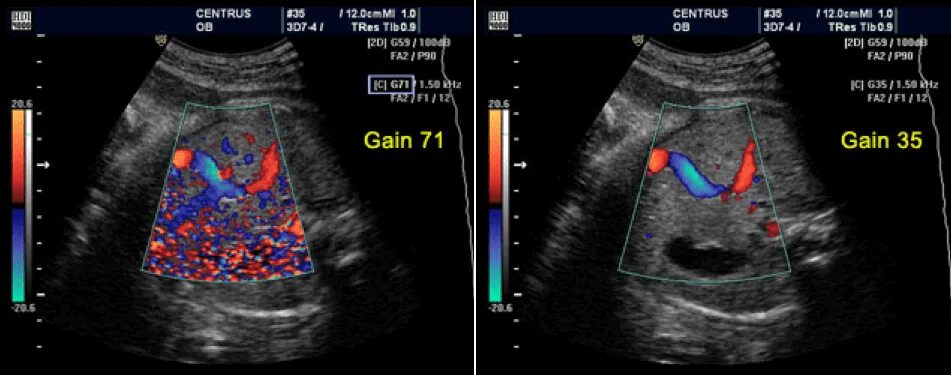

Что такое при цдк